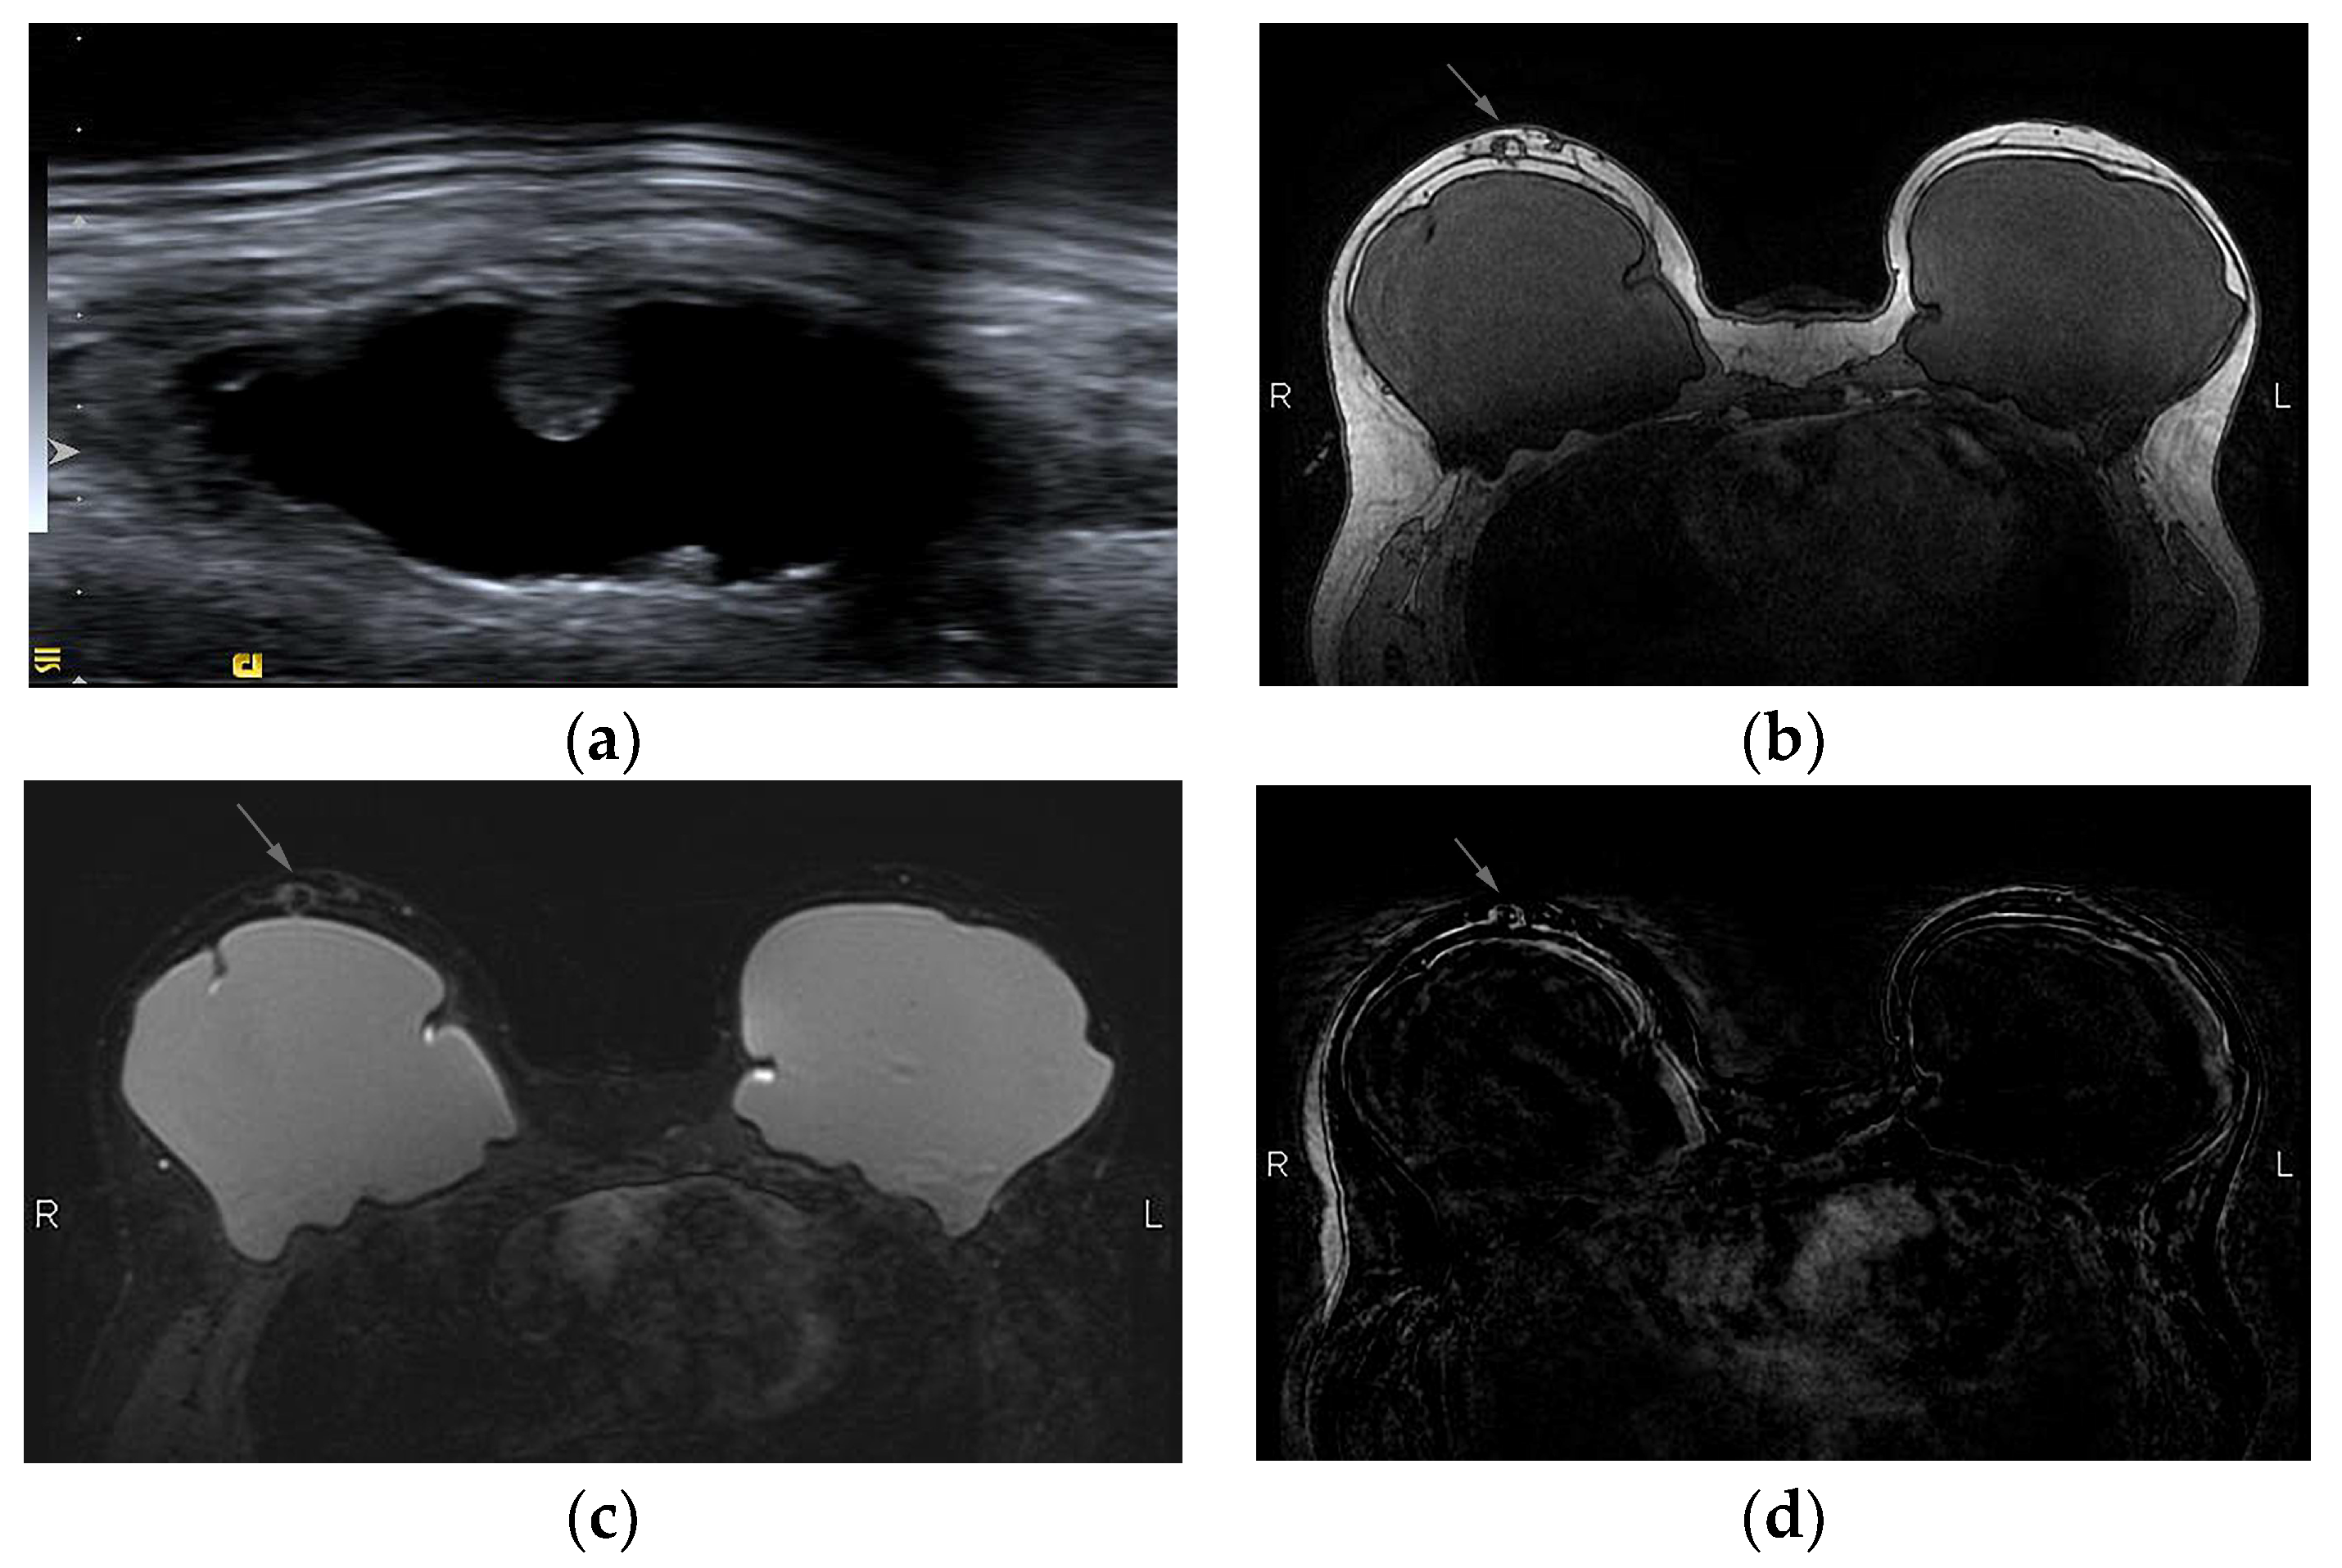

- Adrada, B.E.; Miranda, R.N.; Rauch, G.M.; Arribas, E.; Kanagal-Shamanna, R.; Clemens, M.W.; Fanale, M.; Haideri, N.; Mustafa, E.; Larrinaga, J.; et al. Breast implant-associated anaplastic large cell lymphoma: Sensitivity, specificity, and findings of imaging studies in 44 patients. Breast Cancer Res. Treat. 2014, 147, 1–14. [Google Scholar] [CrossRef] [PubMed]

- Rotili, A.; Ferrari, F.; Nicosia, L.; Pesapane, F.; Tabanelli, V.; Fiori, S.; Vanazzi, A.; Meneghetti, L.; Abbate, F.; Latronico, A.; et al. MRI features of breast implant-associated anaplastic large cell lymphoma. Br. J. Radiol. 2021, 94, 20210093. [Google Scholar] [CrossRef]